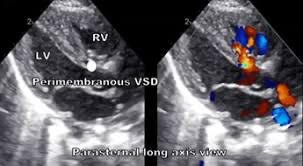

막주위형 (Perimembranous VSD): 가장 흔한 형태로, 약 80%를 차지함. 결손부위가 대동맥 판막 바로 아래에 위치

진단: 심초음파